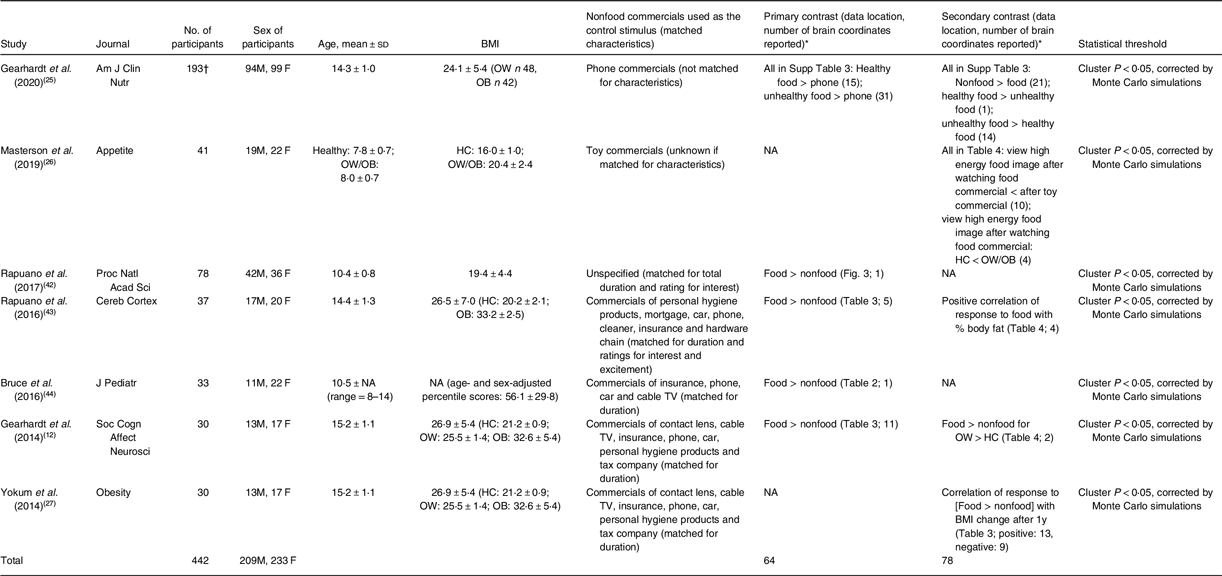

A number of items were extracted from the analysed papers, such as patient age, sex and BMI, commercials used as the control, statistical threshold used to report fMRI results, the number of brain coordinates reported and whether food or nonfood commercials activated the brain more (Table 1).

Table 1 Details of the seven meta-analysed papers

HC, healthy controls. OB, participants with obesity. OW, participants with overweight.

* Unless otherwise specified, food and nonfood mean food and nonfood commercials, respectively.

† The reported results were based on 171 participants (after 22 were excluded) without detailed final sample composition.

There were seven papers entering the meta-analysis, published in between 2014 and 2020 in journals with impact factor. The number of participants per study ranged from 30 to 193. Regarding the mean age of the participants, the means reported from the studies fell within the range of 7·8–15·2 years (Table 1). They all recruited participants in nearly equal sex ratio. The mean BMI from the studies fell within the range of 19·4–26·9 kgm−2, and many of the studies recruited participants across the spectrum of normal weight, overweight and obesity. The nonfood commercials varied in context but were usually matched for duration. Meanwhile, only one paper reported results of nonfood > food commercials(Reference Gearhardt, Yokum and Harris25), whereas most papers reported that food commercials triggered larger brain responses than nonfood commercials.